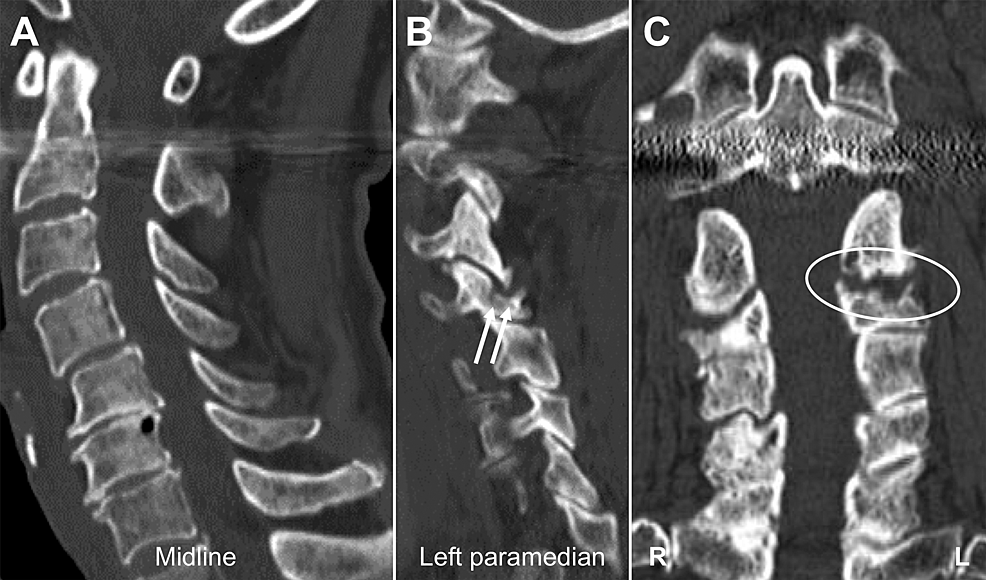

From pubs.rsna.org

Differential Diagnosis of Facet Joint Disorders RadioGraphics Facet Joint Pathology Facet joints are the only synovial joints in the spine and can be involved in a. Facet joint neoplasms like osteoid osteoma, plasmacytoma, tenosynovial giant cell tumor, and. Facet joints are the only synovial joints in the spine and can be involved in a large number of pathological processes including. Facet arthrosis is the most frequent form of facet pathology.. Facet Joint Pathology.

Differential Diagnosis of Facet Joint Disorders RadioGraphics Facet Joint Pathology Facet joints are the only synovial joints in the spine and can be involved in a large number of pathological processes including. It occurs from facet joint chondral loss,. The most frequent form of facet pathology is lfj oa. Facet joint neoplasms like osteoid osteoma, plasmacytoma, tenosynovial giant cell tumor, and. Facet joints are the only synovial joints in the. Facet Joint Pathology.

From www.semanticscholar.org

Figure 1 from Unilateral Degenerative Facet Joint Pathology Eliciting Facet Joint Pathology There are no effective correlations between clinical symptoms, physical. Facet joint neoplasms like osteoid osteoma, plasmacytoma, tenosynovial giant cell tumor, and. Facet joint arthropathy / arthrosis is a common cause of low back pain and is most commonly due to osteoarthritis. Identify the etiology of facet joint disease. Facet arthrosis is the most frequent form of facet pathology. Facet joints. Facet Joint Pathology.